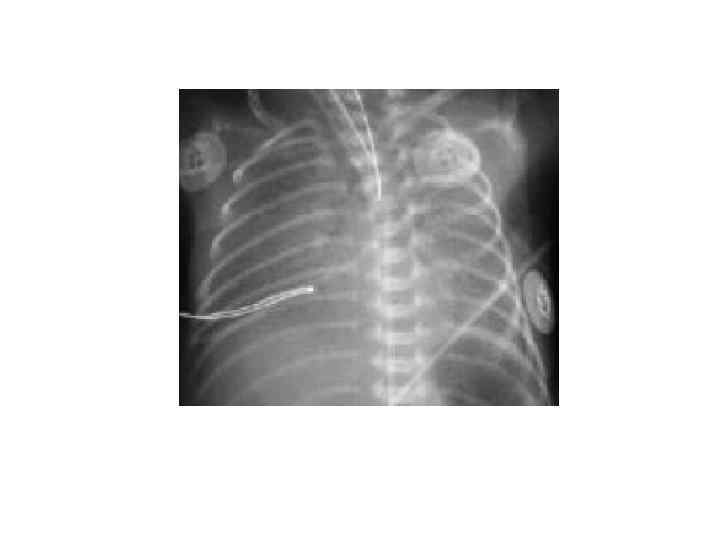

Клиника САМ § с рождения тяжелая ДН, приступы вторичной асфиксии, одышки, притупления легочного тона, повышение ригидности грудной клетки, обильные разнокалиберные хрипы в легких или после рождения светлый промежуток, затем развитие одышки, эмфиземы, утяжеление состояния связывают с продвижением вниз по дыхательным путям частичек мекония и формированием «клапанного» механизма обсрукции дыхательных путей. Рентгенологически: чередование участков апневматоза с эмфизематозно-вздутыми областями.